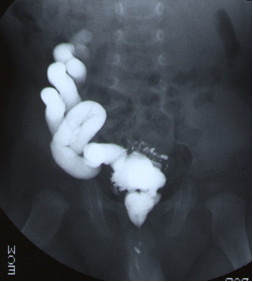

Dziewczynka 3-miesięczna została przywieziona do Izby Przyjęć z powodu wysokiej gorączki. W badaniu przedmiotowym zwracał uwagę twór wystający poza wargi sromowe (patrz obrazek). Jakie rozpoznanie jest najbardziej prawdopodobne?

U 9-miesięcznego chłopca z zakażeniem układu moczowego w wywiadzie, wykonano cystografię mikcyjną (patrz poniższe zdjęcie). Jakie badania należy wykonać w następnej kolejności?